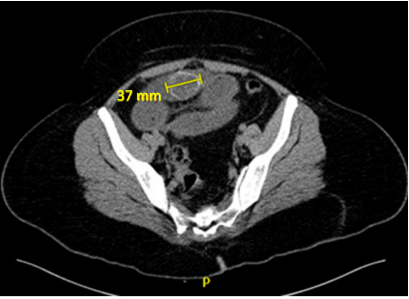

Laboratory tests showed electrolyte imbalance in 14 patients (87.5%) and liver function tests abnormalities in five patients (31.2%). A correct preoperative diagnosis of GI was reached in 13 patients (81.2%); the remaining was diagnosed during surgery. The classical image signs of GI were visualized in 7 patients (43.7%) on plain abdominal radiograph (Figure 1), in six patients (37.5%) on ultrasound (Figure 2) (Figure 3), and in 13 patients (81.2%) on CT (Figure 4) (Figures 5a & b).

Figure 1 Plain abdominal radiograph showing a radio-opaque 34mm-image located in the right upper quadrant suggestive of a gallstone.

Image findings included radio-opaque image suggestive of a gallstone in 11 patients (68.7%), (Figure 6) bowel distention in 10 patients (62.5%) (Figure 7), and pneumobilia in 8 patients (50%) (Figure 8), all classical signs of Rigler´s triad.7